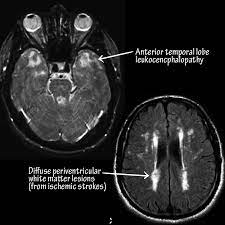

Maladie De Cadasil